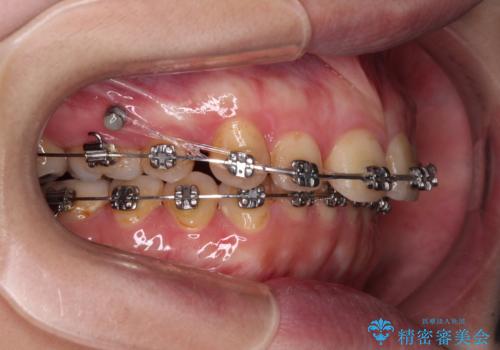

- 矯正装置

- メタルブラケット

- 治療計画

- 上下の前歯が接触しないくらいに突出した上顎前歯を気にして来院された患者様です。

上顎が前方に傾斜して突出しており、下顎前歯は上顎の歯肉に咬みこむような、前後に大きなズレがあり非常に深い咬み合わせとなっていました。

根本的な解決には上顎骨を切除する外科矯正を検討するべきですが、手術無しでの治療をご希望とのことで、上顎左右の第一小臼歯を抜歯してワイヤー装置にて矯正治療を行うこととしました。